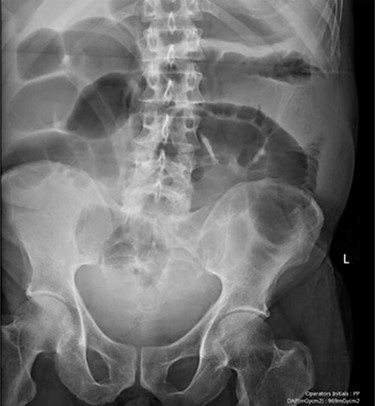

Blood tests on admission were unremarkable. Each admission, the patient’s plain abdominal films showed dilated large bowel loops consistent with sigmoid volvulus (Fig. 1). A subsequent computed tomography (CT) of the abdomen and pelvis with intravenous contrast revealed dilated large bowel and was reported as sigmoid volvulus with no evidence of perforation (Fig. 2). Caecal volvulus was not appreciated on this scan.

Case one: plain abdominal film showing dilated large bowel and the ‘coffee bean’ sign associated with sigmoid volvulus.

Case one: coronal slice of a CT scan of the abdomen and pelvis with intravenous contrast showing dilated large bowel.